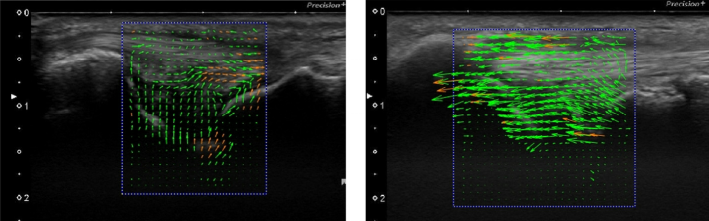

이 연구에서는

'입자 영상 유속계(PIV)'라는

특수 분석 기법으로 관절원판이 움직이는

'속도'를 측정했는데요.

@ https://doi.org/10.3390/s22010345

좌측 건강한 그룹에 비해서

우측 손상된 환자 그룹의 TFC가

더 빠르고 과하게 움직이는 것으로

밝혀졌습니다.